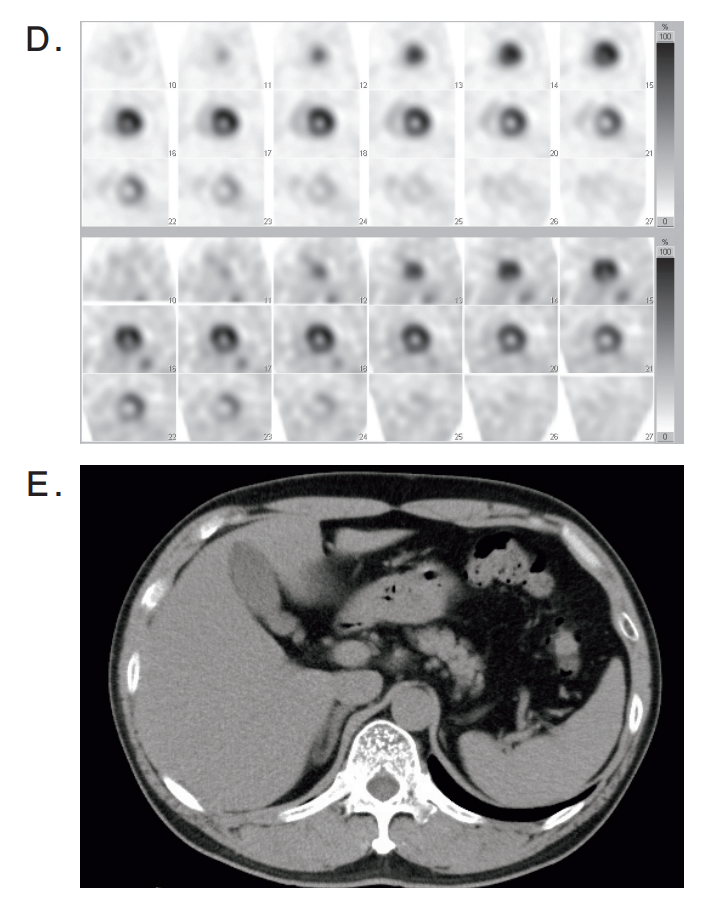

検査の画像を別に示す。

狭心症(angina pectoris)の手術に最も重要な検査はどれか。